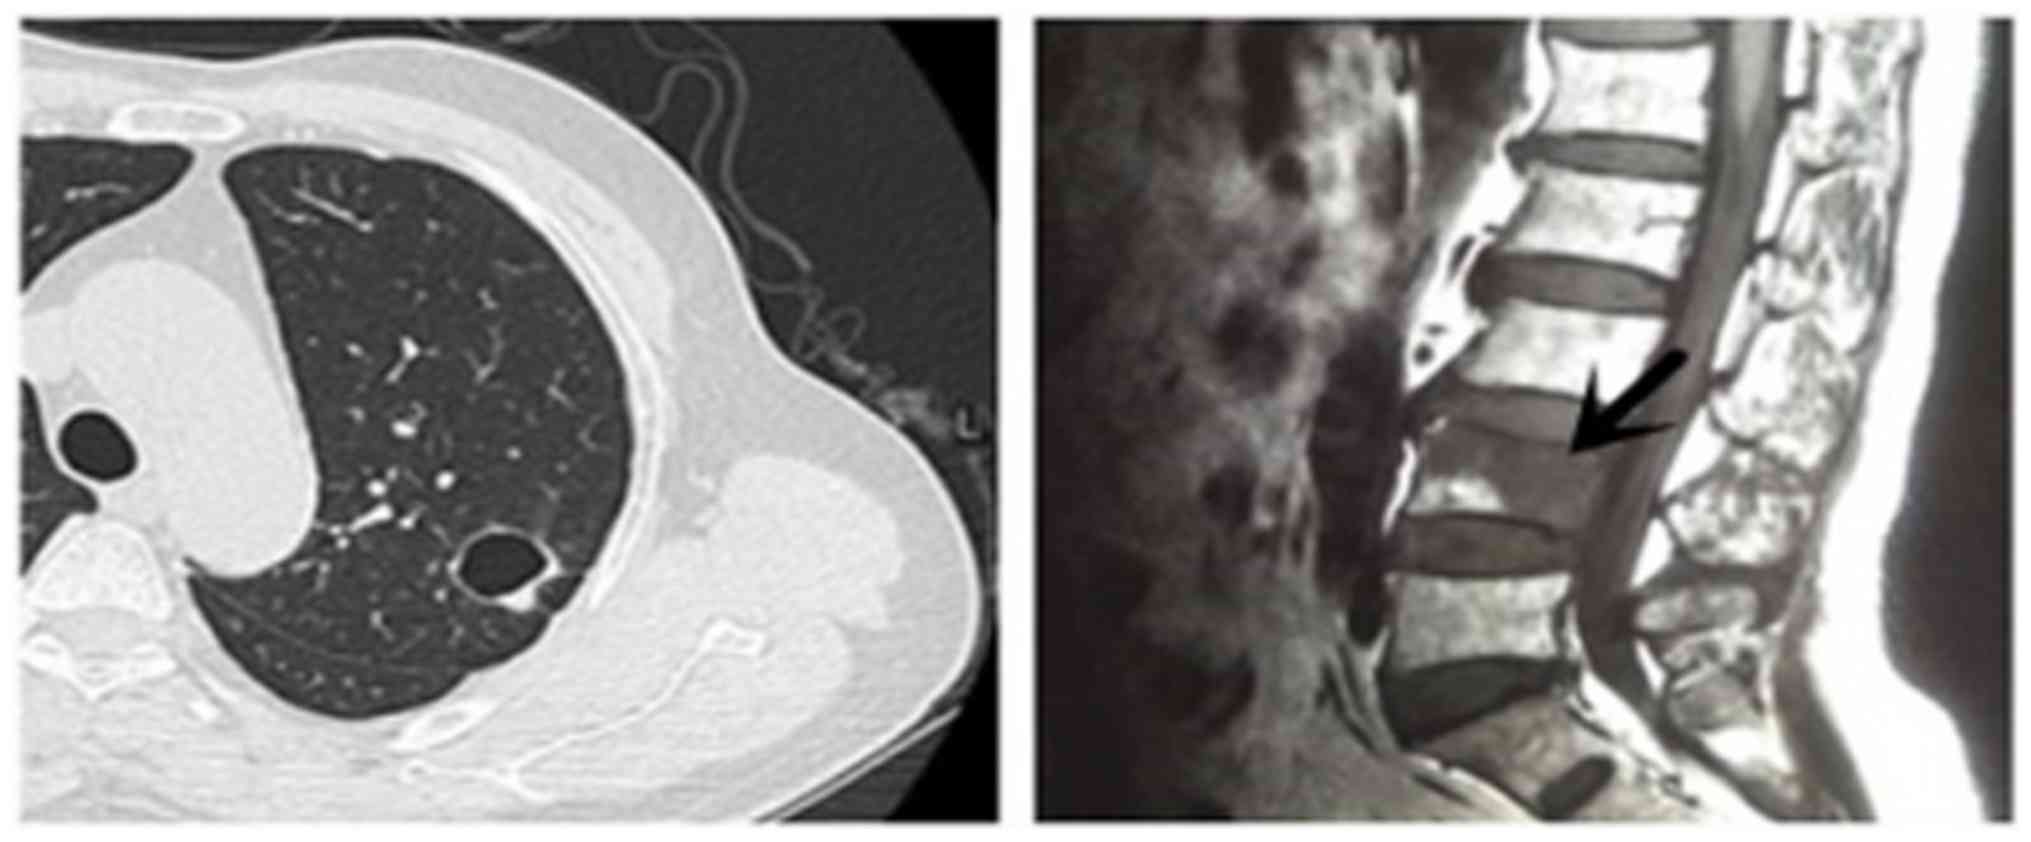

Metastasis to the fourth lumbar vertebra was noted in the whole-body bone scan of one patient (Fig. 2), which was confirmed as metastatic adenocarcinoma by pathological findings following percutaneous needle washing (PNW).

One 33-year-old patient with a 2-month history of cough and sputum presented with a large, abnormal cystic lesion in the left lung and multiple cystic lesions in the two lungs on CT images (Fig. 3). The diagnosis by CT and PET/CT was pulmonary bullae. Pleural involvement, repeated pneumothorax and choking sensations in the chest were evident. Due to these signs, the possibility of malignant lesions was not ruled out. Therefore, bronchoscopic biopsy was performed, which confirmed these cystic lesions as intrapulmonary metastatic adenocarcinoma.